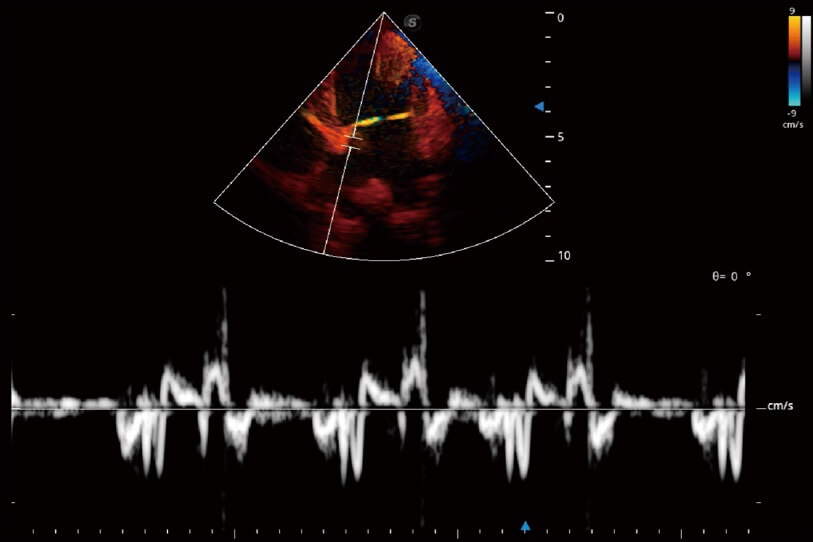

实时用颜色表示心肌组织运动,观察和定量组织的运动情况,对快速检测与评估心肌的灌注和活性、电传导及心肌收缩和舒张功能等均能提供重要的诊断信息。